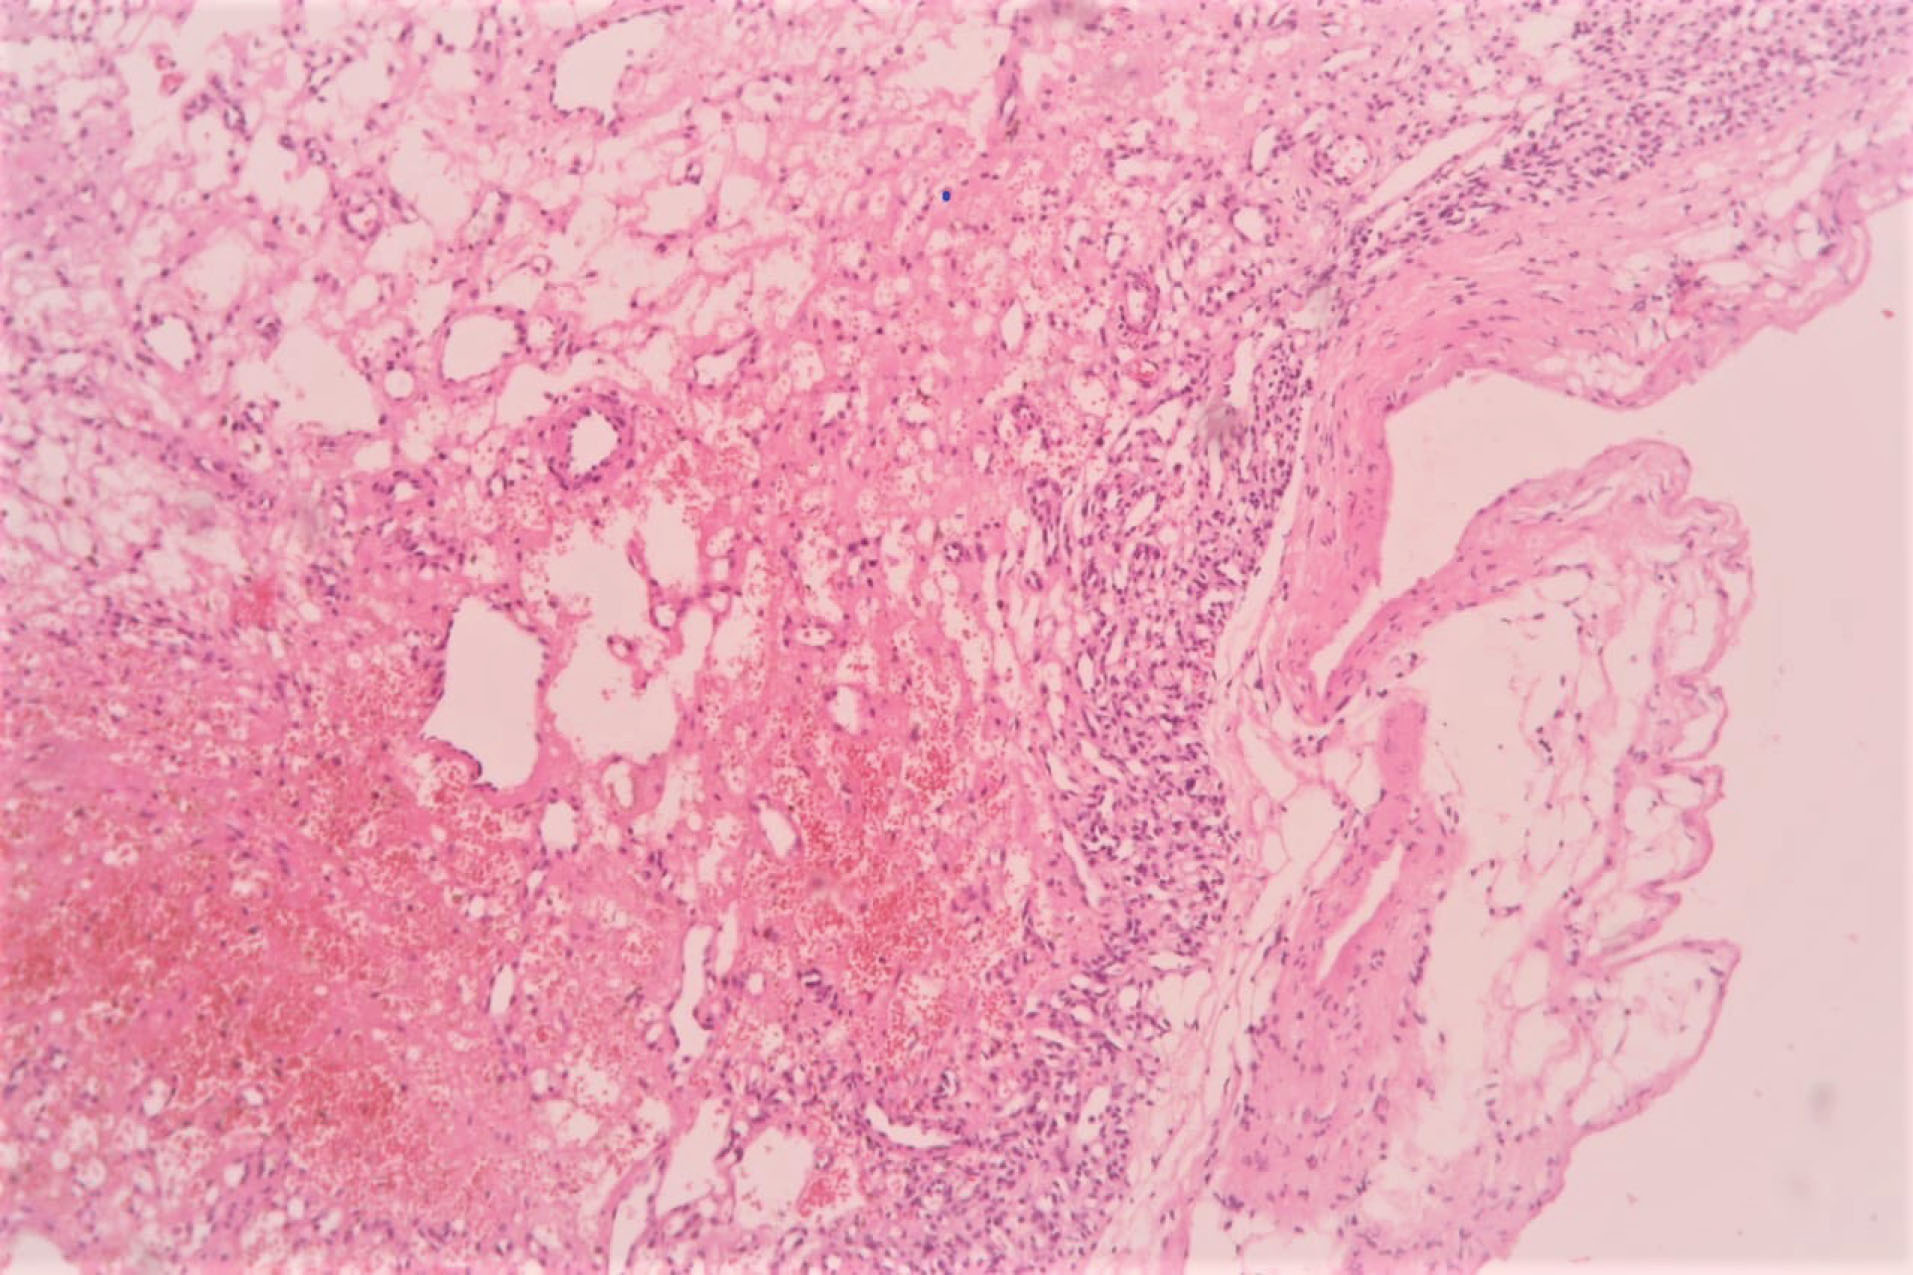

The patient underwent midline sternotomy under general anaesthesia for planned pericardial window surgery with diagnostic and therapeutic intent for the mass after thorough preoperative workup including ultrasonography of Abdomen and pelvis region. After opening pericardium, we found encapsulated, firm, highly vascular mass immediately adjacent to the main pulmonary artery and extending towards the posterior wall of right ventricle. Since the mass seems to be part of the right ventricular wall, resectability was deemed as difficult. Hence, only careful partial mass resection without any cardiac reconstruction was done after taking pledgeted polyprolene sutures around planned excision areas, to prevent torrential bleeding or cardiac rupture. Overlying total pericardium was removed to make left sided pleuropericardial window. Procedure went smoothly and post operatively patient did well. The histopathology examination revealed multiple vascular like structures and small capillary type vessels suggestive of a capillary type haemangioma without mitosis ( and ). She is currently asymptomatic with no recurrence of any pericardial or pleural effusion after regular follow-up of six months.

jcvtr-13-250-g003

Figure 3. Microscopic view of section shows an encapsulated tumour composed of numerous small capillary sized vascular spaces, some of which are dilated. These spaces are lined by endothelial cells. Stroma shows areas of oedema and haemorrhage. (x100, Hematoxylin & Eosin).